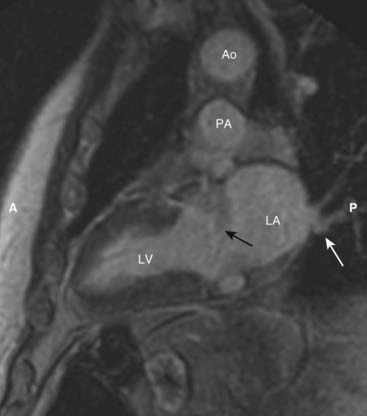

image

Figure 9-31 Cardiac MRI, vertical long axis view.

The vertical long axis or two-chamber view demonstrates the left ventricle (LV) separated from the more posterior left atrium (LA) by the mitral valve area (solid black arrow). Pulmonary veins drain into the left atrium (solid white arrow). The aorta (Ao) sits atop the pulmonary artery (PA). (A is anterior and P is posterior.)